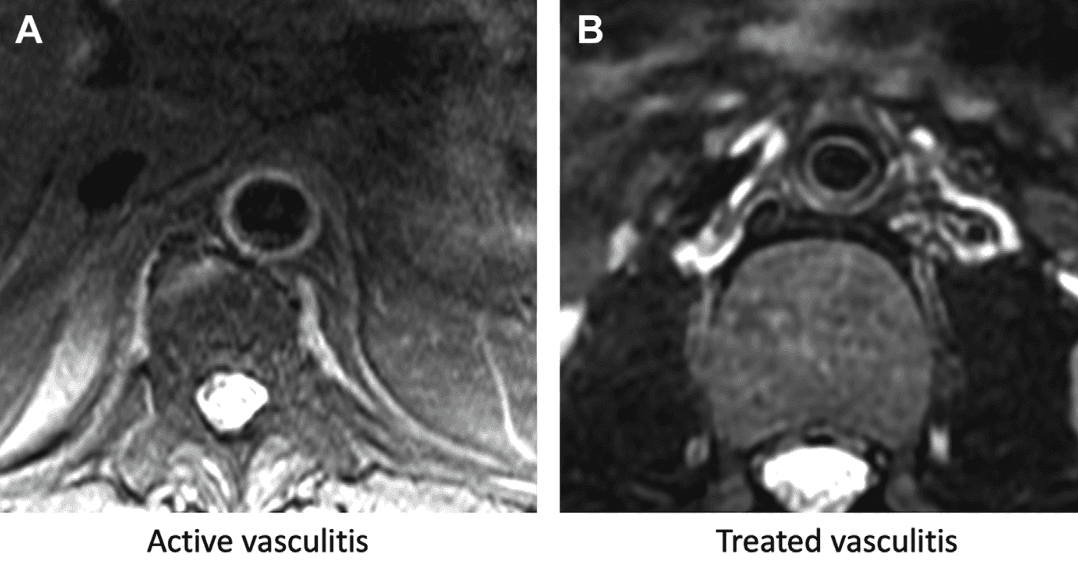

Una de las ventajas diferenciales de la RM es su capacidad para evaluar directamente la pared aórtica. Las secuencias T2-weighted vessel wall imaging permiten identificar edema inflamatorio y distinguir enfermedad activa de enfermedad tratada. En vasculitis activa, el engrosamiento mural acompañado de hiperintensidad T2 orienta a inflamación en curso; cuando la enfermedad ha sido tratada, el engrosamiento puede persistir, pero la señal inflamatoria disminuye. Esta diferencia cambia seguimiento, tratamiento y timing clínico.